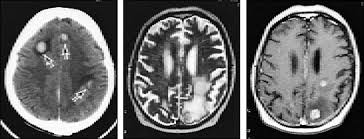

Signs Of Metastatic Breast Cancer In Brain / How Research Is Failing Women With Metastatic Breast Cancer Time : They are usually named after the tissue or organ where the cancer first developed (for example, metastatic lung or breast cancer tumors in the brain, which are the most.. Metastatic brain tumors (also termed secondary brain tumors) are made of cancerous cells that spread through the bloodstream from a tumor located elsewhere in the body. Webmd medical reference reviewed by brunilda nazario. Metastasis is most often found when people report symptoms, such as bone pain, to. Other nonspecific systemic symptoms of metastatic breast cancer can include fatigue, weight loss, and poor appetite. The incidence of brain metastasis from breast cancer (24 % in this review) is increasing due to advances in both imaging technologies leading to earlier detection of the brain metastases and introduction of novel therapies resulting in longer survival from the primary breast cancer.

An overview of the presentation, diagnosis. Webmd medical reference reviewed by brunilda nazario. Sometimes people with metastatic breast cancer do not have any of these changes. Metastatic cancer can display general symptoms and symptoms at specific sites of metastasis. Metastatic breast cancer, also referred to as metastases, advanced breast cancer, secondary tumors, secondaries or stage iv breast cancer, is a stage of breast cancer where the breast cancer cells have spread to distant sites beyond the axillary lymph. Signs and symptoms of metastasis. Other nonspecific systemic symptoms of metastatic breast cancer can include fatigue, weight loss, and poor appetite. Metastatic cancer that spreads from its original location is known by the name of the primary cancer. After lung cancer, metastatic breast cancer is the second most common cancer associated with brain metastases in the united states 1. Signs of cancer in the brain include headaches, seizures, vision changes, and dizziness. Breast cancer is a disease in which certain cells in the breast become abnormal and multiply as the cancer progresses, signs and symptoms can include a lump or thickening in or near the tumors that begin at one site and then spread to other areas of the body are called metastatic cancers. They are usually named after the tissue or organ where the cancer first developed (for example, metastatic lung or breast cancer tumors in the brain, which are the most. The cancer has spread to other parts of the body.

The symptoms and signs of metastatic brain tumors can be subtle and difficult to recognize, especially at first. The cancer has spread to other parts of the body. This usually includes the lungs, liver, bones or brain. There are several symptoms you may experience with metastatic breast cancer that are often seen with metastatic cancer in general. After lung cancer, metastatic breast cancer is the second most common cancer associated with brain metastases in the united states 1.

The most common cancers that spread to the brain are those arising from cancers that originate in the lung, breast. Sometimes, metastatic disease may not cause any symptoms. Systemic treatment of metastatic breast cancer. Metastatic brain tumors are five times more common than primary brain what are the signs and symptoms of metastatic brain tumor? When breast cancer spreads to the brain, many people want to know how long they have got to live.

Metastasis is most often found when people report symptoms, such as bone pain, to. Systematic analysis of breast cancer morphology uncovers stromal features associated with survival. Signs and symptoms caused by brain metastases can vary based on the location, size and rate of growth of the metastatic tumors. The incidence of brain metastasis from breast cancer (24 % in this review) is increasing due to advances in both imaging technologies leading to earlier detection of the brain metastases and introduction of novel therapies resulting in longer survival from the primary breast cancer. For example, cancer that has spread from the breast to the brain. What you experience usually relates to where the tumor is and its size. Metastatic cancer can display general symptoms and symptoms at specific sites of metastasis. We often find these tumors when testing for other conditions or when investigating the stage of your primary cancer. Learn about them and when to talk to your doctor. Signs and symptoms of metastasis. Groaning, grimacing, or appearing restless could be signs that a. Webmd medical reference reviewed by brunilda nazario. (redirected from stage iv breast cancer).